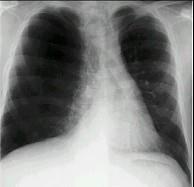

问题 男性,62岁。吸烟史40余年,近10年来气急进行性加重。胸部X线检查见图。关于此诊断的X线征像下列哪一条是不需要的 ( )

选项 A.肋间隙增宽 B.膈肌位置降低 C.膈穹窿变平坦 D.肺野透亮度降低 E.肺大疱

答案 D